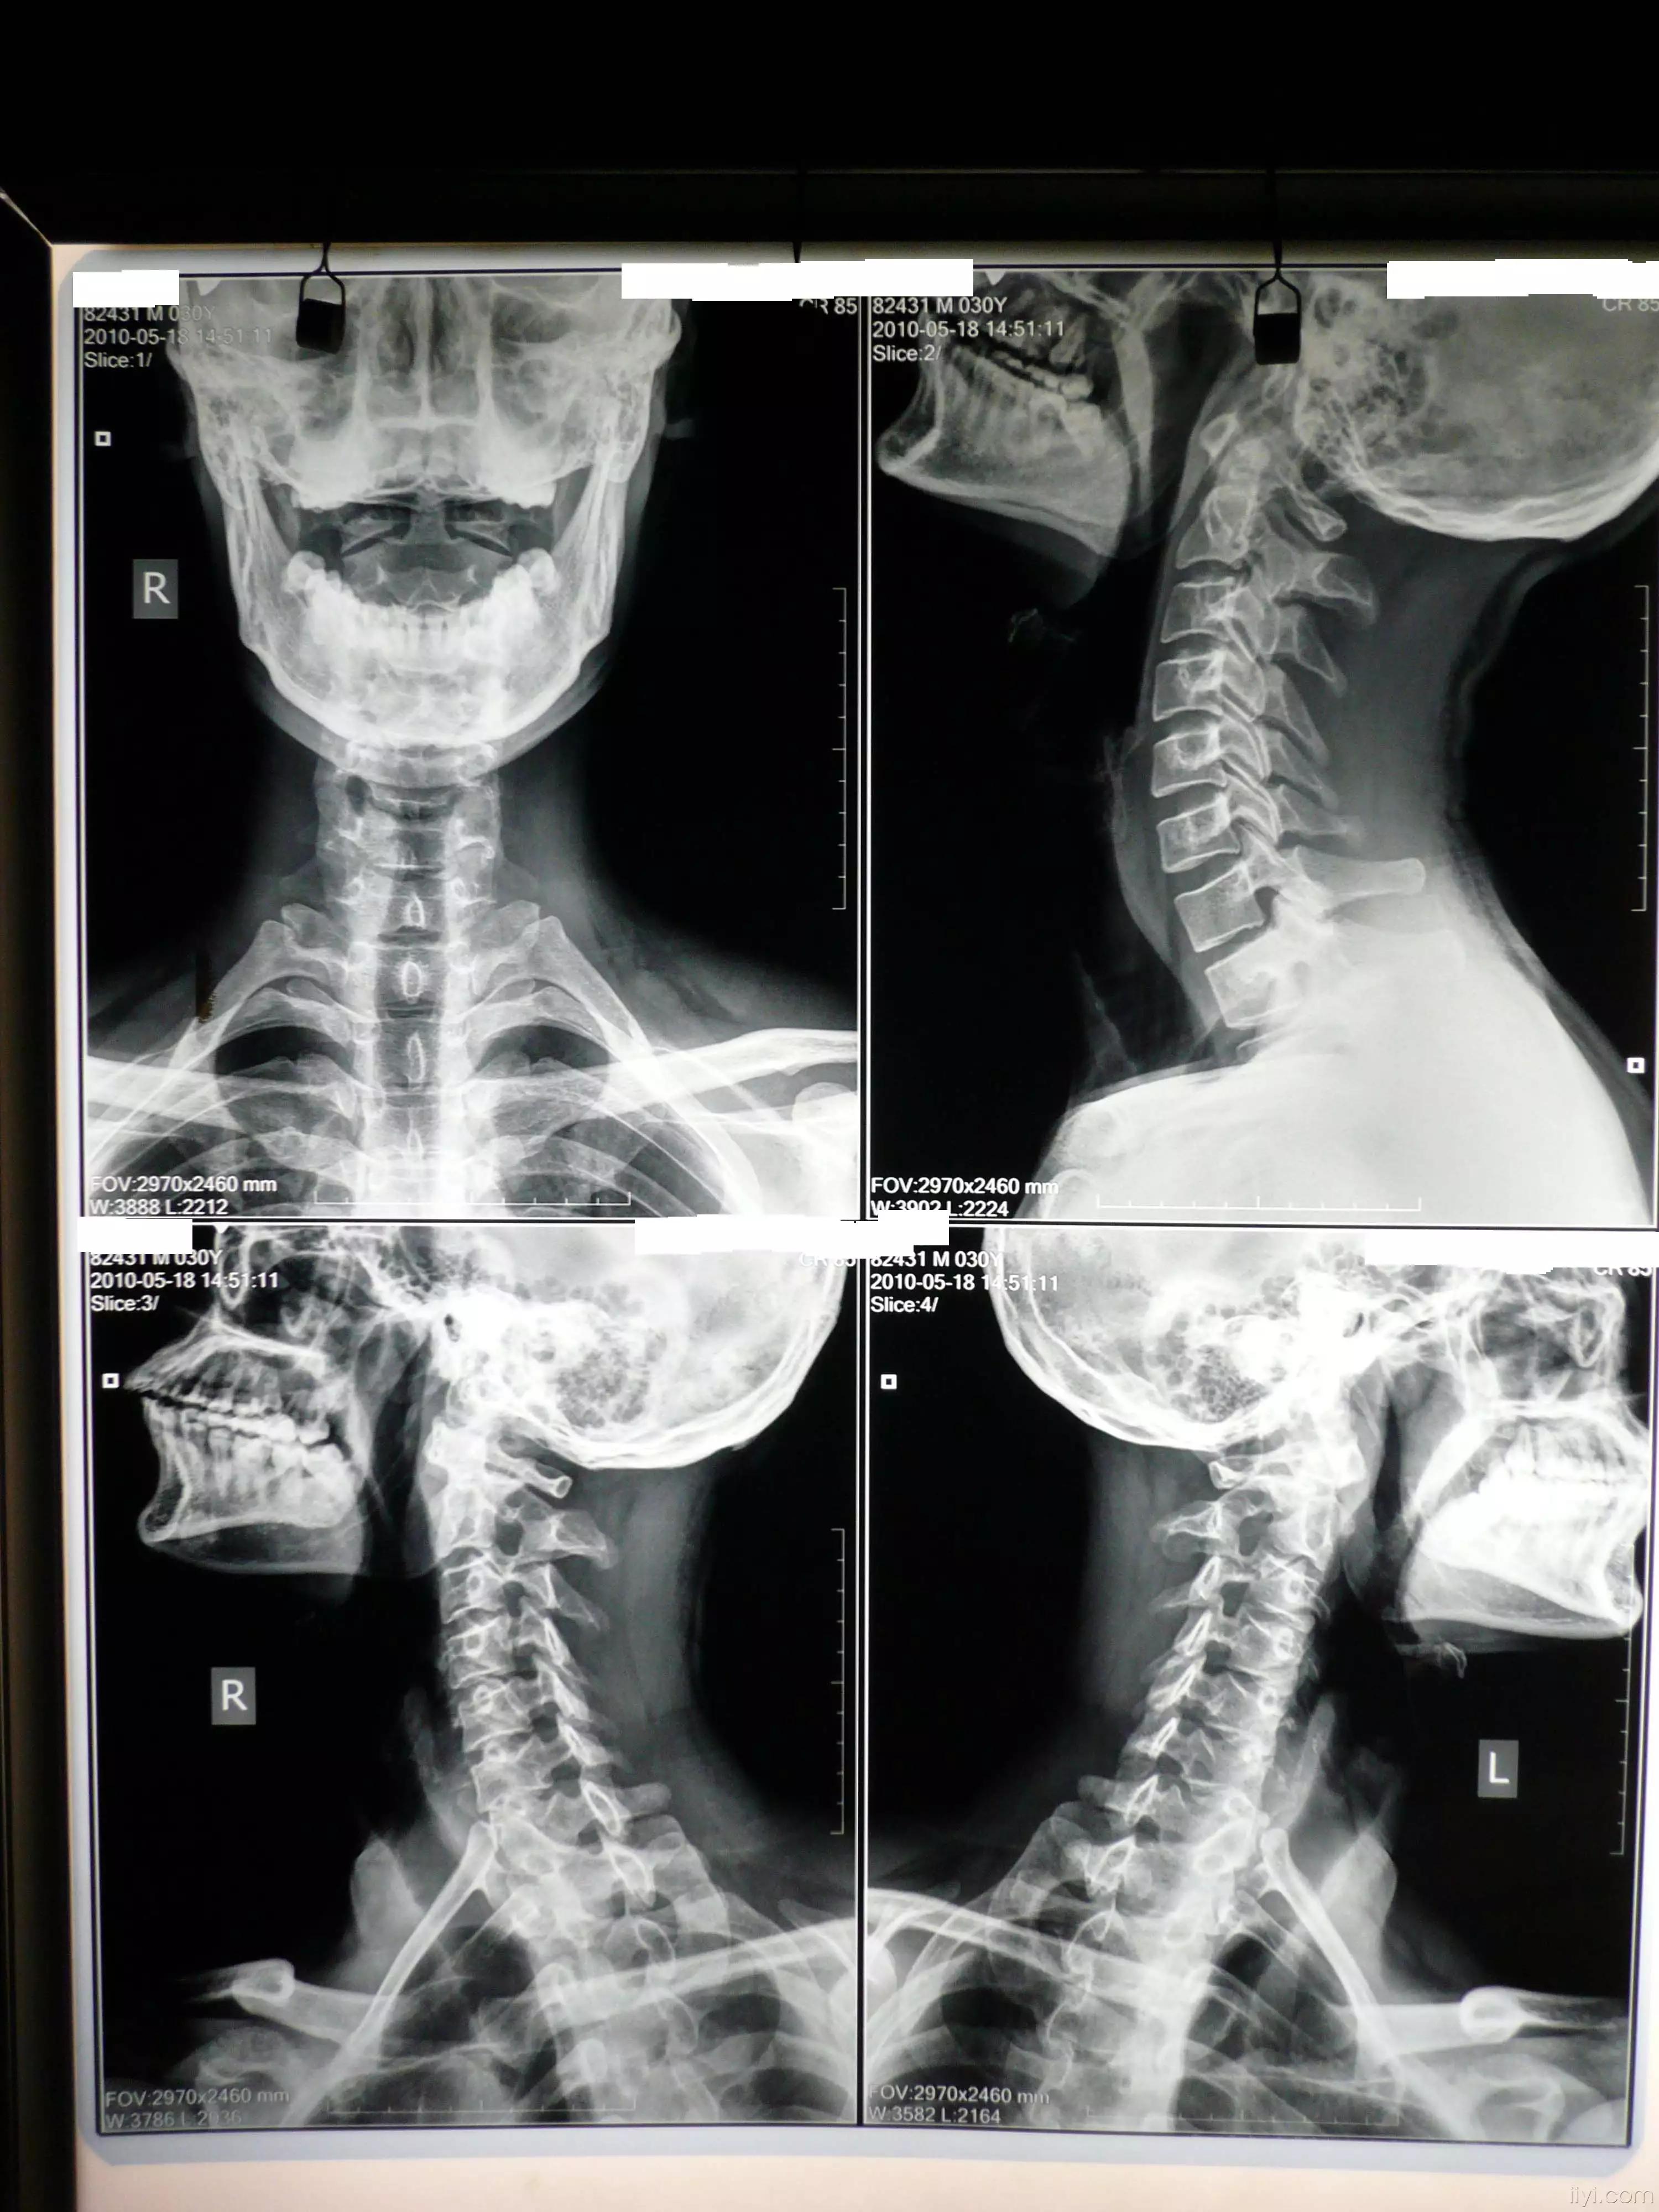

颈椎正位,双侧位,正侧位片